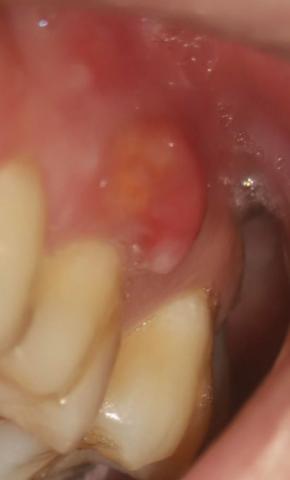

Dental Case Analysis – Large Red Gum Swelling Near Posterior Tooth

This intra-oral image shows a large, red, swollen lesion on the gum tissue adjacent to a posterior tooth. The appearance is consistent with an active localized gum infection, likely involving deeper periodontal tissues and possibly the underlying bone if not treated promptly.

Full Analysis and Diagnosis

Clinical Findings

Prominent red, dome-shaped swelling on gingiva

Inflamed, shiny soft tissue